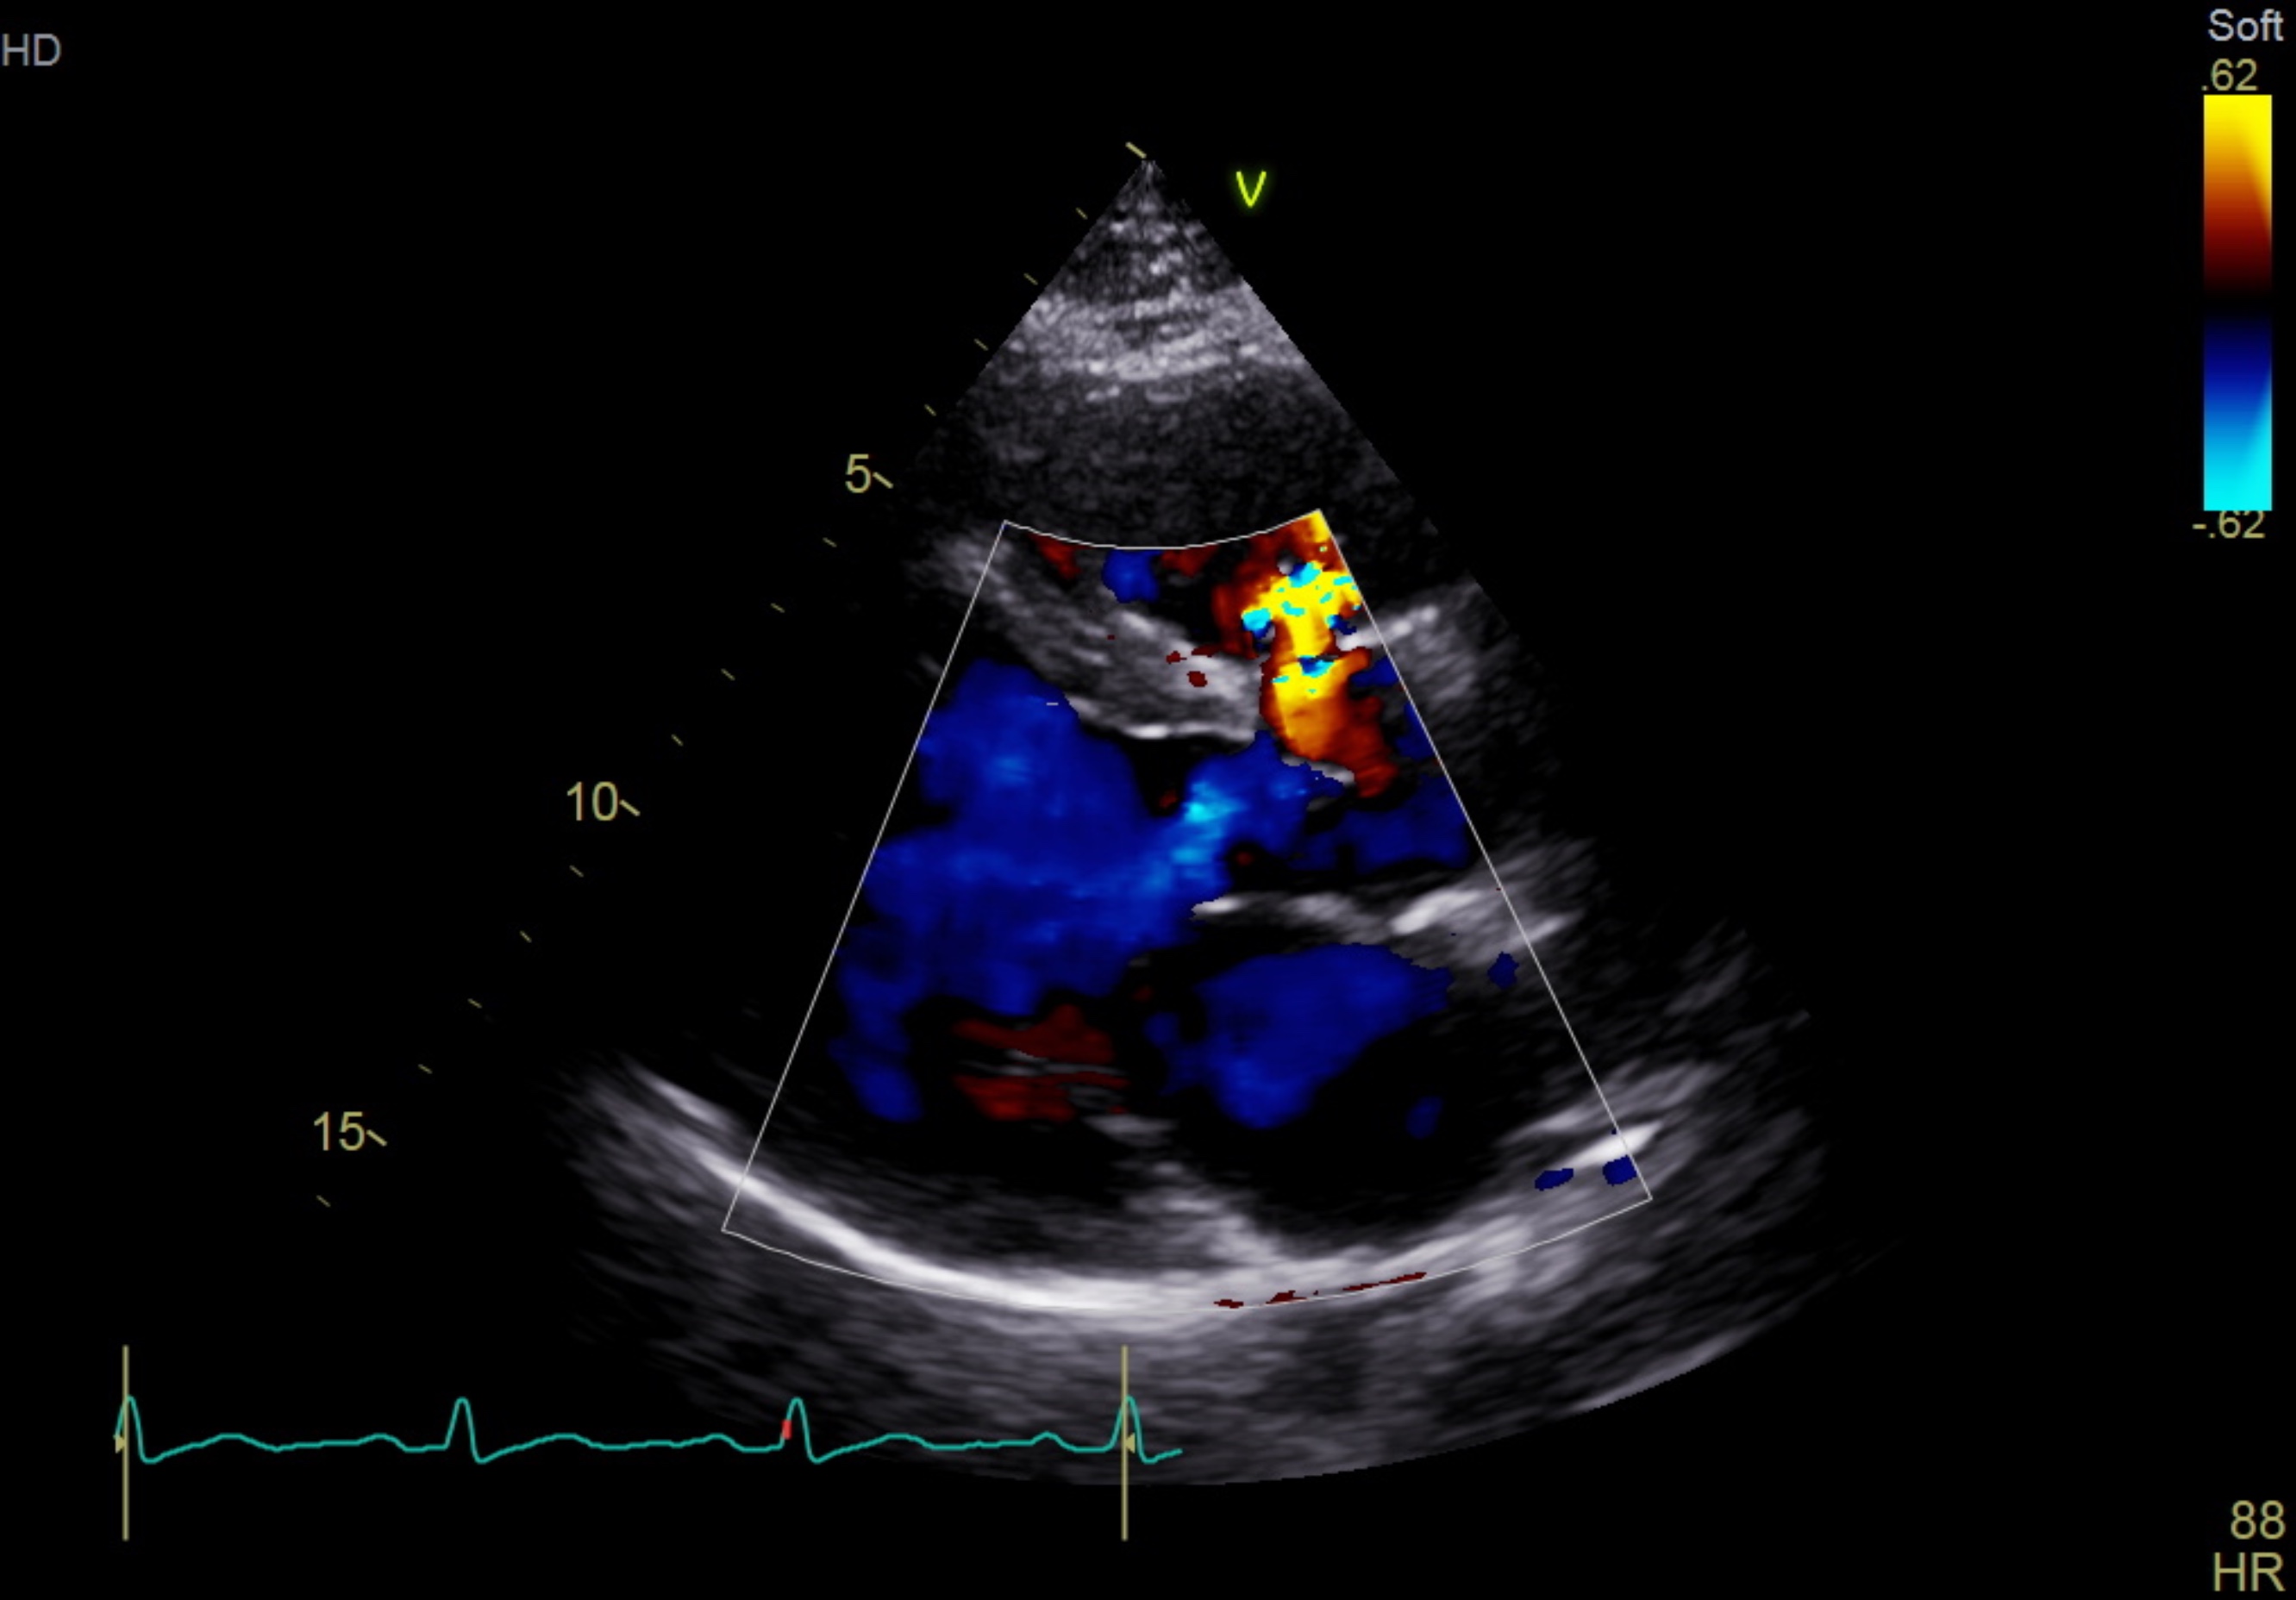

The electrocardiogram shows sinus rhythm, normal axis with left ventricular hypertrophy. The chest X-ray shows a normal cardiac silhouette without prominent pulmonary trunk. His NT-ProBNP was raised with normal troponin reading.The trans-thoracic echocardiogram revealed a ruptured right sinus of valsalva (SOV) with left to right shunting to right ventricle. The aorta is dilated without aortic valve regurgitation. The left ventricle is dilated with 63% of ejection fraction.

PLAX CFM.mp4